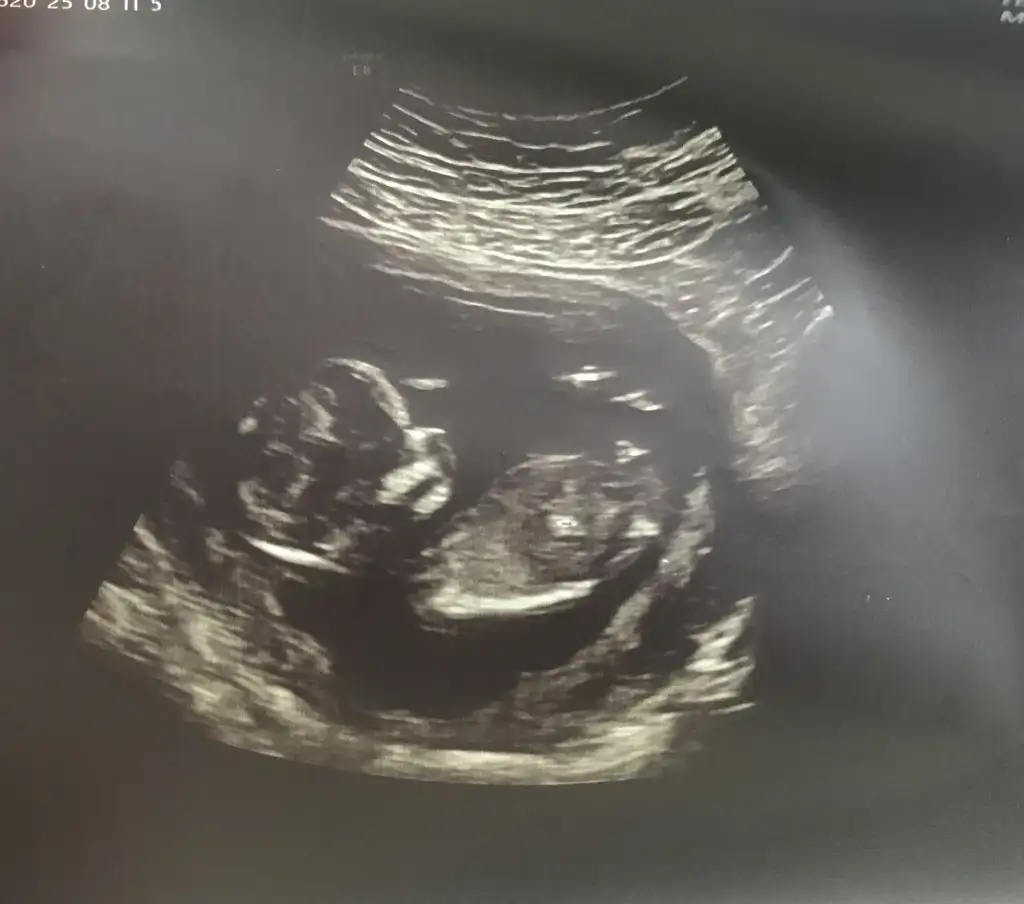

13 haftalık ultrason fotoğrafına göre cinsiyet tahmini?

Bu arkadaşımın 13+3 net değil demişler sizce erkek mi kız mı

Bakın işte burada 3 çizgi🥰 Ama henüz yeni yeni oluştuğu için yanılma payı olabiliyor tabiki😊 Gönlünüzdeki nasip olur inşallah, sağlıcakla